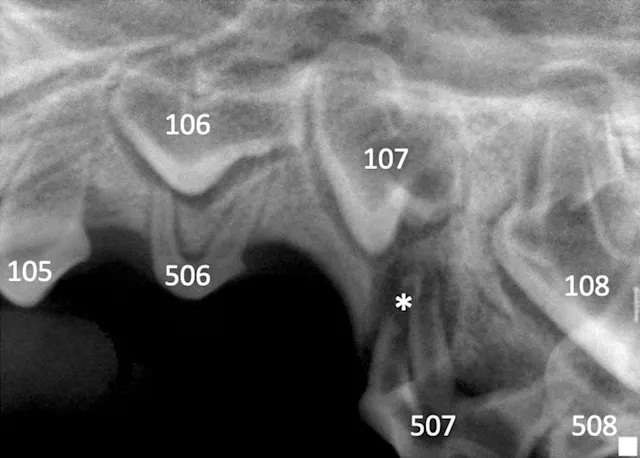

Dental radiography via a veterinary digital intraoral sensor and oral examination were performed with Uma under anesthesia. A slab fracture was seen on the palatal surface of 507 with pulpal exposure (Figure 2); a probe was easily inserted into the pulp cavity. No abnormalities were noted on the left side (Figure 3). Radiographs of the fractured tooth and its contralateral counterpart revealed a radiolucent area at the apexes of the mesial (ie, rostral, side of the tooth directed toward the first incisor) roots of 507.